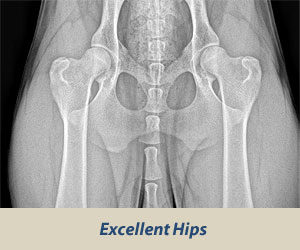

For this reason, we must start with good genetics but also look beyond them to secure the best hip quality outcomes for our dogs. Drahthaar and other breeders continue to leverage additional practices to reduce the likelihood of HD in puppies after birth. A critical time period is while the neonates are with the breeder, who can take certain steps to create an environment inimical to HD. This responsibility is then picked up by owners who typically take home their puppies around 8-10 weeks, as HD seems to develop during the rapid growth period of the first 6-7 months of a dog's life. Some indications that a dog will develop hip dysplasia are already quite evident before the first year is up. For example, one study demonstrated that young Labrador Retrievers with high (>0.7) distraction index scores have a high probability of developing hip osteoarthritis.(5) Actually, some HD and OA symptoms may even be visible as early as several weeks after birth, such as wear and tear type tissue damage.(6) Because HD may still be developing throughout the first year, radiographs to screen breeding dogs are typically only taken after a dog is at least 12-24 months of age. Specific positioning is required that often necessitates dogs are under anesthesia to maximize their comfort and the image quality of the resulting picture.

Excerpted from the Orthopedic Foundation for Animals: https://www.ofa.org/diseases/hip-dysplasia

See also PennHIP testing, which uses distraction index scores: https://antechimagingservices.com/antechweb/pennhip